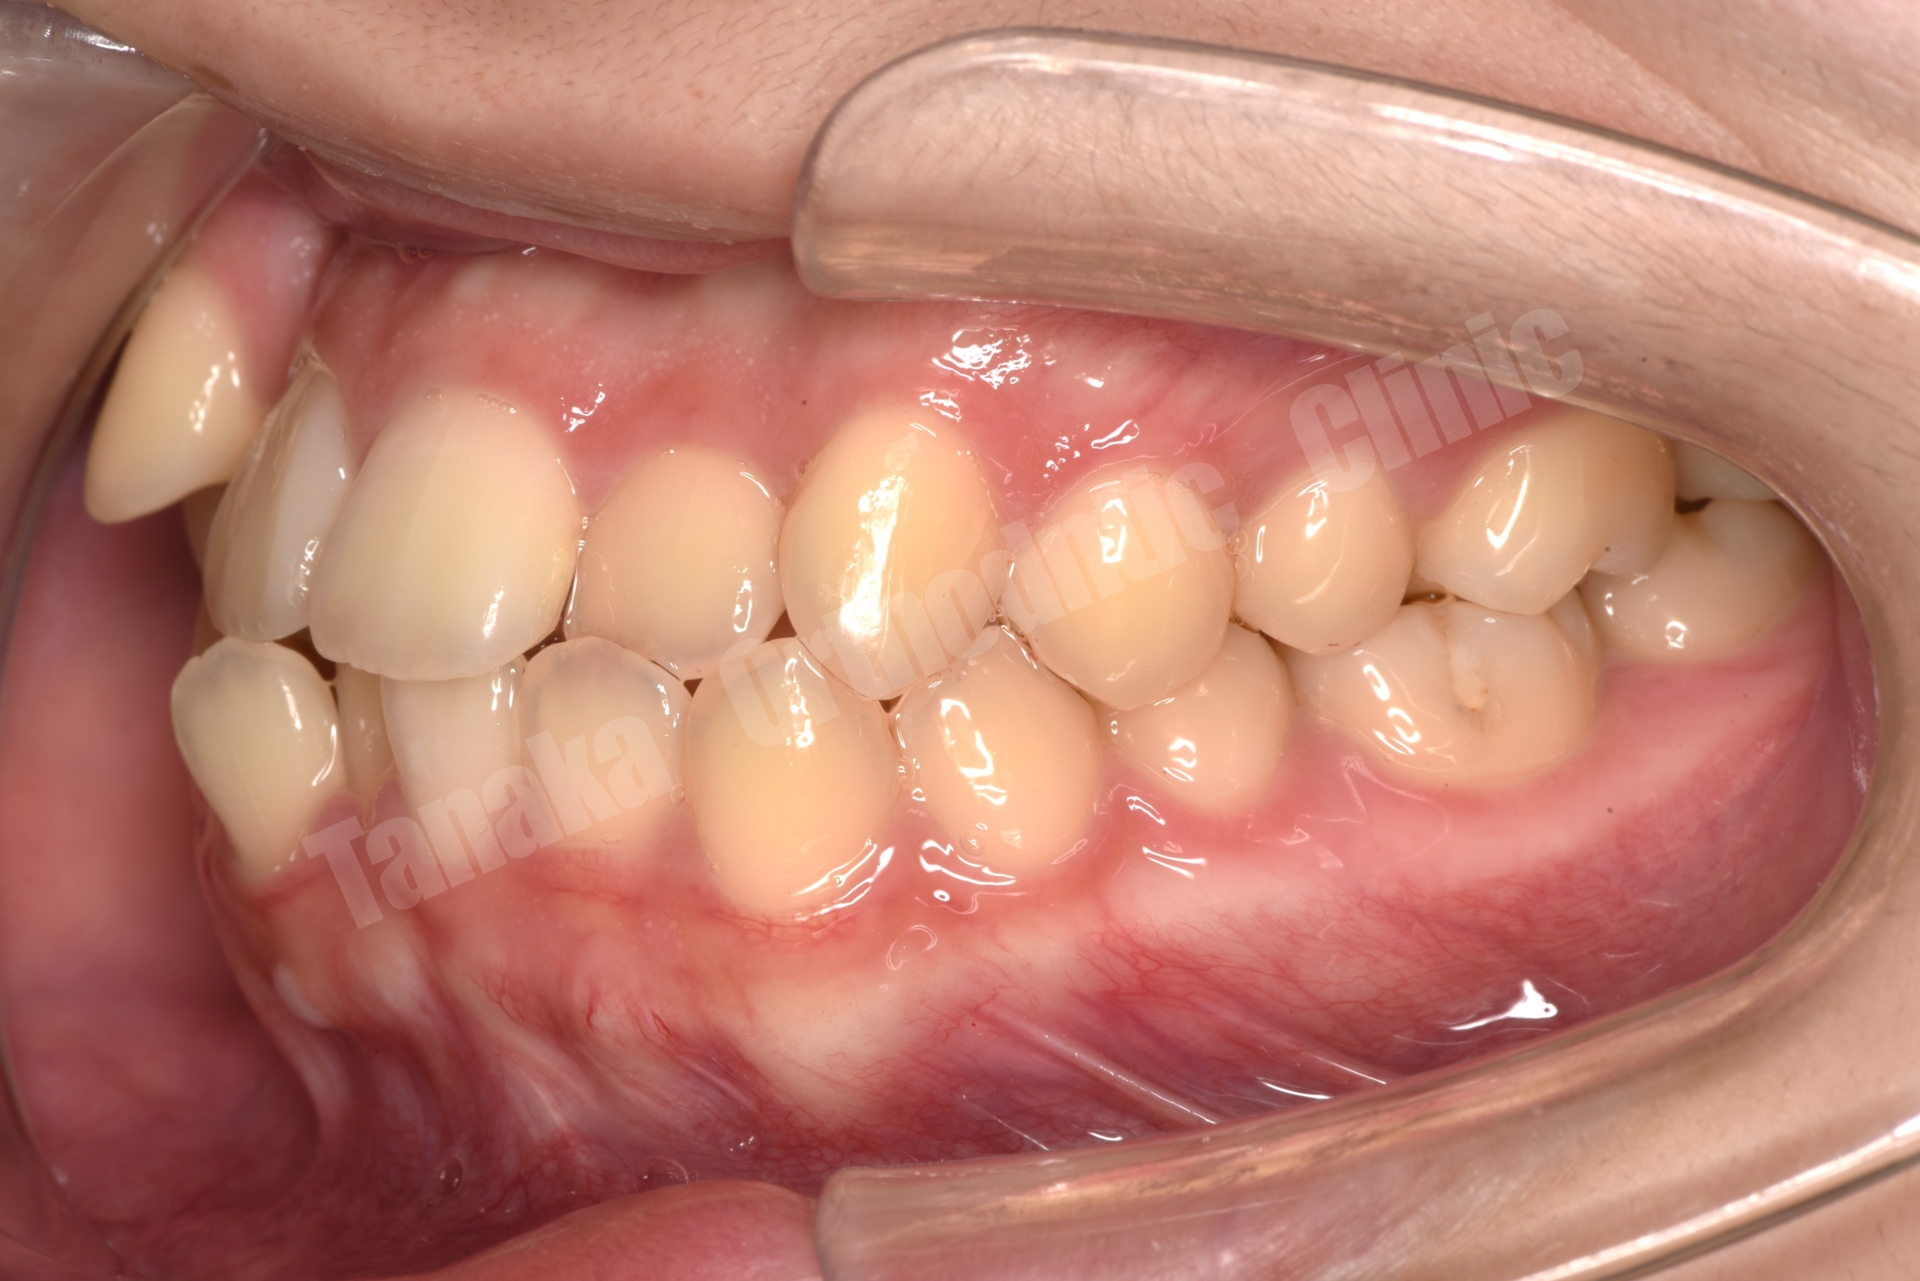

| 主訴 | 八重歯(13.23)、上顎正中の右偏位、下顎前歯のガタガタ |

| 診断 | 下顎前突(上顎後退傾向&下顎前突傾向)、上下顎歯列の叢生(上顎右側3番完全唇側転位&上顎正中の右偏位)、上下左右8番を認める |

上下顎叢生(13完全唇側転位)